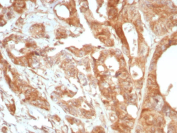

Glycoprotein 36 Antibody Prostate IHC. Immunohistochemistry analysis of Glycoprotein 36 / PDPN expression in FFPE human prostate tissue using recombinant Glycoprotein 36 antibody, clone PDPN/8875R. HRP-DAB brown staining is observed in stromal and perivascular regions with membranous and cytoplasmic localization, while glandular epithelial cells show comparatively reduced signal; nuclei are counterstained blue. This Glycoprotein 36 antibody highlights PDPN-associated stromal compartments consistent with its known distribution. Antigen retrieval was performed by boiling sections in 10 mM Tris buffer with 1 mM EDTA, pH 9, for 20 min followed by cooling at room temperature.